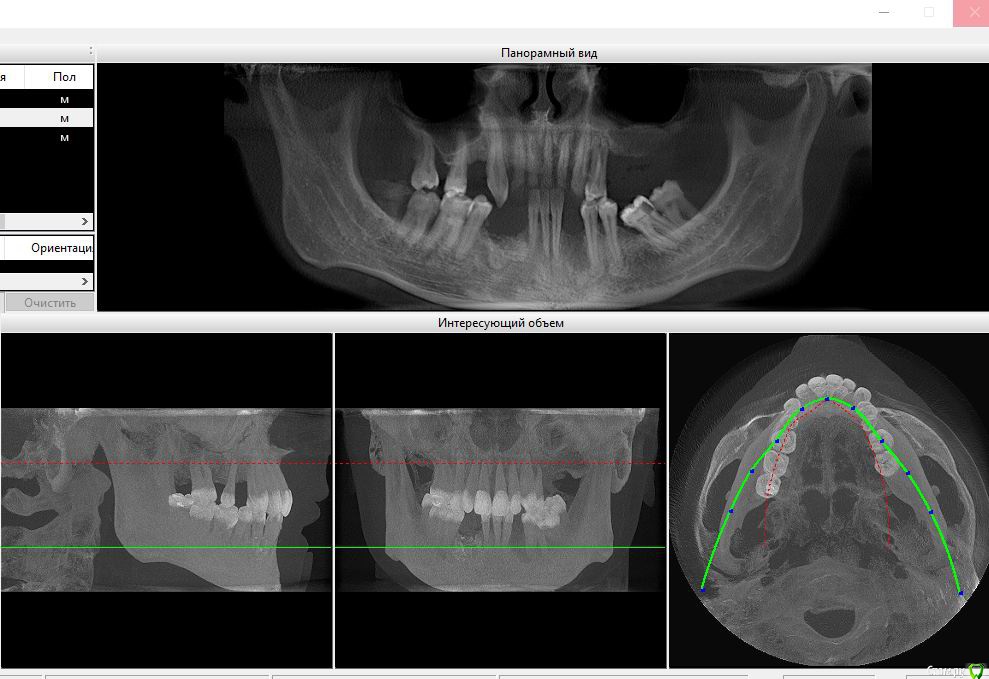

smile32 Опубликовано 28 августа, 2017 Поделиться Опубликовано 28 августа, 2017 (изменено) 38 лет, первый зуб расшатался еще в 2010. К тому моменту по другим причинам уже были удалены 4 зуба.Была скученность зубов. Вредных привычек (сигареты, алкоголь) нет.На данный момент уже нет 12 зубов. Врач поставил диагноз генерализованный пародонтит. Сейчас начинают болеть и оголяться и верхние передние зубы.Подскажите, это можно как-то остановить? Или посоветуйте врача\клинику в России? Изменено 28 августа, 2017 пользователем smile32 1 Ссылка на комментарий

Neilrus Опубликовано 30 августа, 2017 Поделиться Опубликовано 30 августа, 2017 Боюсь тенденция продолжиться, вам нужен комплексный подход (терапевт, ортопед, хирург) с удалением еще как минимум 6 зубов (судя по снимку) и дальнейшим ОБЯЗАТЕЛЬНЫМ протезированием съемными или несъемными протезами...конкретного ответа как остановить без очного осмотра никто вам не даст, к сожалению, а врача найти можете в соответствующем разделе 3 Ссылка на комментарий